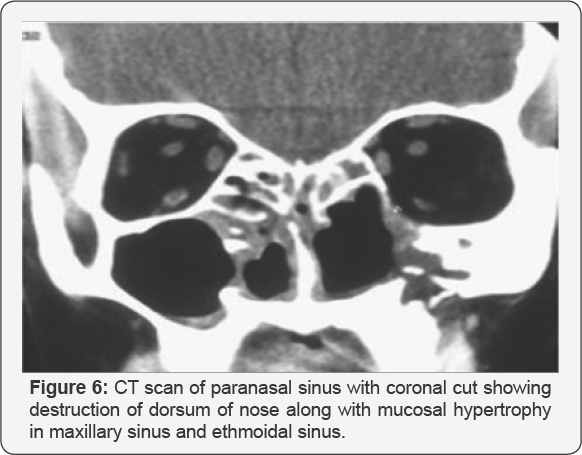

Because NK/T-cell lymphoma of the head and neck is an extremely rare malignancy, there is not in function a protocol standard for the treatment but should be discuss in a mixed team including planning \with hematologists, oncologists, and radiation oncologists. Currently the most recommended treatment includes CHOP (Cyclophosphamide, doxorubicin, vincristine, prednisone) chemotherapy in conjunction with radiotherapy. The combination of treatments has yielded 5-year survival rates ranging from 20% to 80%, unfortunately, with a high rate of relapse rate, Also they have a very a high degree of resistance to standard therapy. For these patients, alternative strategies have been investigated with some success. Highdose chemotherapy with or without total-body irradiation, followed by Autologous stem cell rescue, has been used for patients with relapsing disease. More recently, new treatments using the SMILE protocol (dexamethasone, methotrexate, ifosfamide, l-asparaginase, and etoposide) show promising results but adverse effects, including significant myelotoxicity, suggest more research is needed to further develop this promising protocol. Treatment regimen for early stage nasal NKTL that included radiotherapy combined with infusion intra- arterial, through the superficial temporal artery, of ifosfamide, carboplatin, methotrexate, peplomycin, and etoposide. Surgical management of patients with NKTK-Lymphoma is limited to biopsy, stabilization of the airway if necessary, debunking of disease in case of hemorrhage-ligation of the ECA ,IMA ,cauterization ,laser Reconstruction in case of positive stable response Patients refractory to treatment or with high-risk can benefit from hematopoietic stem cell transplantation. Because of the relatively high mortality, low response rate, and high relapse rate after definitive treatment, patients should be regularly monitored by an otolaryngologist Figure 6 [11-20].

vi. The diagnosis of mid facial NK/T-cell lymphoma is based on the histopathological picture, immunophenotype of the atypical cells and the analysis of T-cell receptor genes. The surface of the affected site is associated with crusting and necrotic tissue, so the diagnosis of NK/T-cell lymphoma is extremely difficult by taking only punch biopsy, excisional biopsy or deep biopsy is often essential for the diagnosis of this disease. The characteristic histopathological picture in NK/T cell lymphoma shows angiocentric and angiodestructive growth pattern with zonal necrosis. Immunohistochemical study shows positive CD3, CD43, CD45RO, CD20 and CD57 demonstrates the a typical lymphoid cells have T-cell phenotype. Radiological findings in CT scan and MRI are not distinctive for other malignant lesions, typically showing irregular margins, bone destruction and heterogenous contrast enhancement.